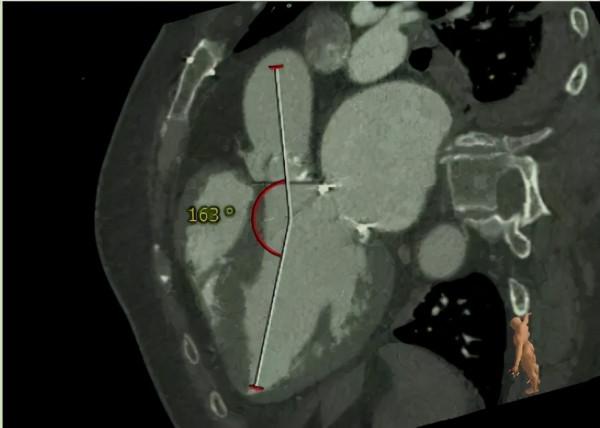

術前,重點根據原生物二尖瓣和自身主動脈瓣的測量資料,選定合適的介入瓣膜型號。

首先,鄭寶石團隊經左前外側胸部小切口,顯露心尖,在荷包線內穿刺,經DSA(數字減影技術)引導下,按預定順序,在主動脈瓣位置成功置入27號J-Valve介入瓣。

接著,黃凱調整導絲方向進入二尖瓣,用球囊預擴狹窄的生物瓣,再置入25號倒裝的J-Valve介入瓣,球囊後擴,完成瓣中瓣置入。